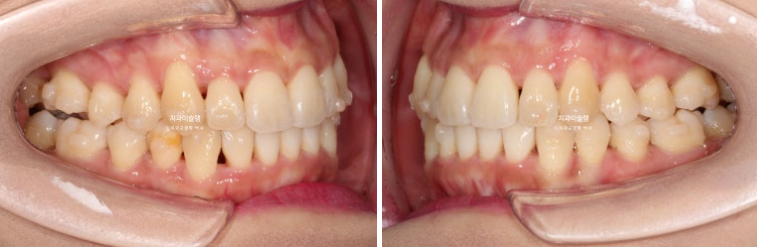

23.08~25.10

하악 사랑니 공간을 이용하여 덧니를 배열했습니다.

이제 안모 비교 해보겠습니다.

아랫입술에 걸쳐지던 송곳니 덧니는 제자리로 잘 들어갔네요

인비절라인 비발치 교정 후 깔끔한 미소와 적절한 앞니 각도가 돋보입니다.